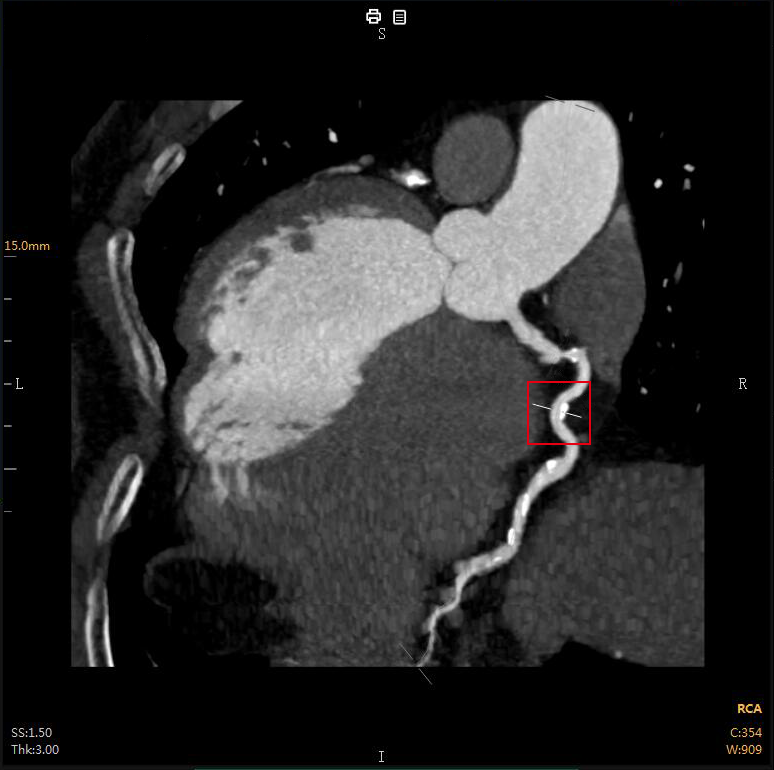

“CTA冠脈全自動(dòng)診斷”

Automatic Coronary Diagnosis

CTA冠脈動(dòng)脈造影以幾乎無(wú)創(chuàng )的方式

成為冠心病的首選檢查

全自動(dòng)圖像重建/分割

全自動(dòng)量化測量

全自動(dòng)結構化報告

全自動(dòng)膠片及電子膠片輸出

云端AI的CTA冠狀動(dòng)脈全自動(dòng)診斷

重構了CTA冠脈檢查的極簡(jiǎn)流程